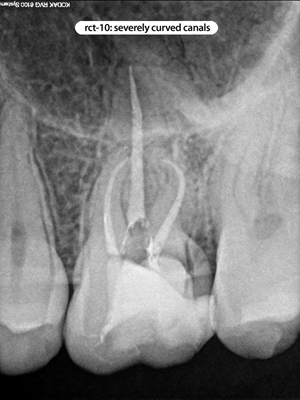

Root Canal Cases